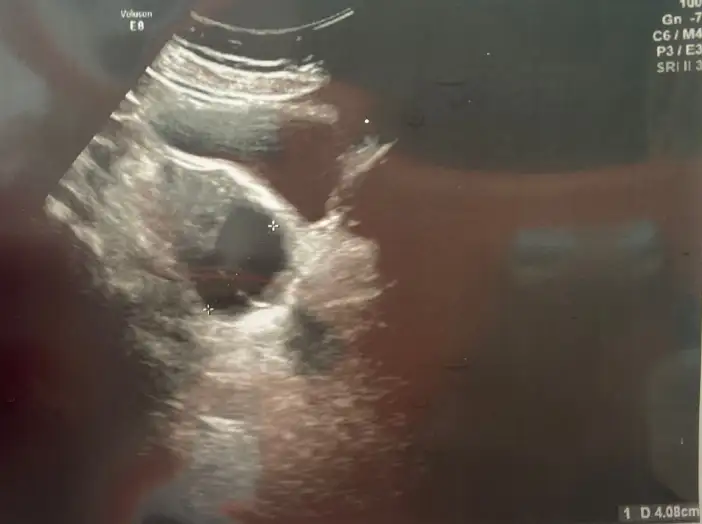

Çıktım canım doktordan nur topu gibi yapışık 4 cm kistim varmış. Bunlar daha önceki kontrollerinde varmıydı doktorun gözünden mi kaçtı yoksa bu döngünde mi oluştu bilemiyoruz. Bunları almaya gerek yok ama bu döngünde atılıp atılmadığına bakıcaz 12. gün tekrar gel dedi. Olmazsa doğum kontrol hapı vericem dedi. Tsh ve fsh ıma baktı aşağıya kist ve raporları ekliyorum. Kist sebebiyle doğum kontrol hapı kullanan olmuşmuydu hiç aranızdaaGünaydın canım benim lekelenme adete çevirdi bugün. Femara kullanıp kullanmamakta kararsızım. Doktordan çıkınca haber ver kuzum

Tsh, fsh normal canım onlarda sorun yok. Soğan kürünü denedin mi hiç canım ben 8cm kistimi attım onun sayesinde doğum kontrol hapını içmekten iyidir diye düşünüyorum. Birdahaki kontrole kadar yapabilirsin benceÇıktım canım doktordan nur topu gibi yapışık 4 cm kistim varmış. Bunlar daha önceki kontrollerinde varmıydı doktorun gözünden mi kaçtı yoksa bu döngünde mi oluştu bilemiyoruz. Bunları almaya gerek yok ama bu döngünde atılıp atılmadığına bakıcaz 12. gün tekrar gel dedi. Olmazsa doğum kontrol hapı vericem dedi. Tsh ve fsh ıma baktı aşağıya kist ve raporları ekliyorum. Kist sebebiyle doğum kontrol hapı kullanan olmuşmuydu hiç aranızdaa(( Moralım çok bozuk